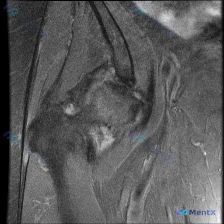

这个肩关节MRI病例,更像盂唇病变还是肩袖问题?

整理了一个肩关节MRI病例,临床问题是评估盂唇病变,但影像分析有几个点值得讨论:

- 冈上肌腱在肱骨大结节附着处信号增高,结构连续性似乎中断

- 肩峰下-三角肌下滑囊有明显积液

- 肱骨大结节区域有骨髓水肿

- 报告提到“冠状位无法全面评估盂唇”